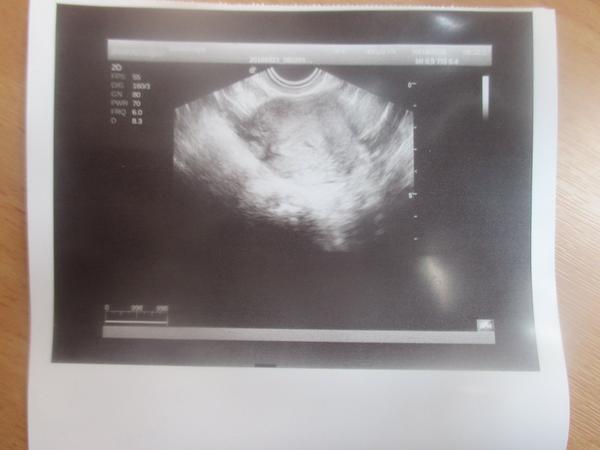

@lussinka88 ahojky když pracuješ v laborce,můžu se tě prosím na něco zeptat? 😀 já mám včerejší výsledky s HCG takto IU/I a mám 26,50 jak to teda je?dnes jsem byla na UTZ,protože mě docela pobolívá podbříšek tak jsem si nechala napsat nemocenskou... a už na UTZ jde vidět malinká tečka (těhotenství) tady je fotka... dr mi hned řekl,že jsem těhotná a ukazoval mi to i na UTZ.on se neplete,ale zase ta hodnota HCG mě plete 😀 když včera byla tak malá tak jak může už dnes něco být na UTZ? 🙂 moc děkuji za vysvětlení 🙂